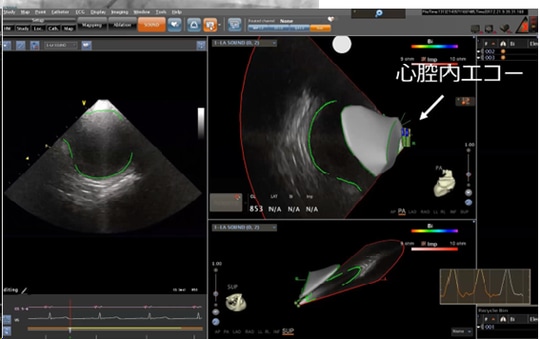

3次元画像システムを使う際には、まず心臓のなかに磁気センサーがついた「心腔内エコー」を入れ、エコー越しに心臓の内部を観察します。

[図表3]は右心房にカテーテルを入れ、左心房を観察しているところです。この画像に基づき、臨床工学技士が左心房をトレースします。すると、次のような図([図表4])が完成します。

左右の図とも、右心房と左心房がきれいにトレースされています。